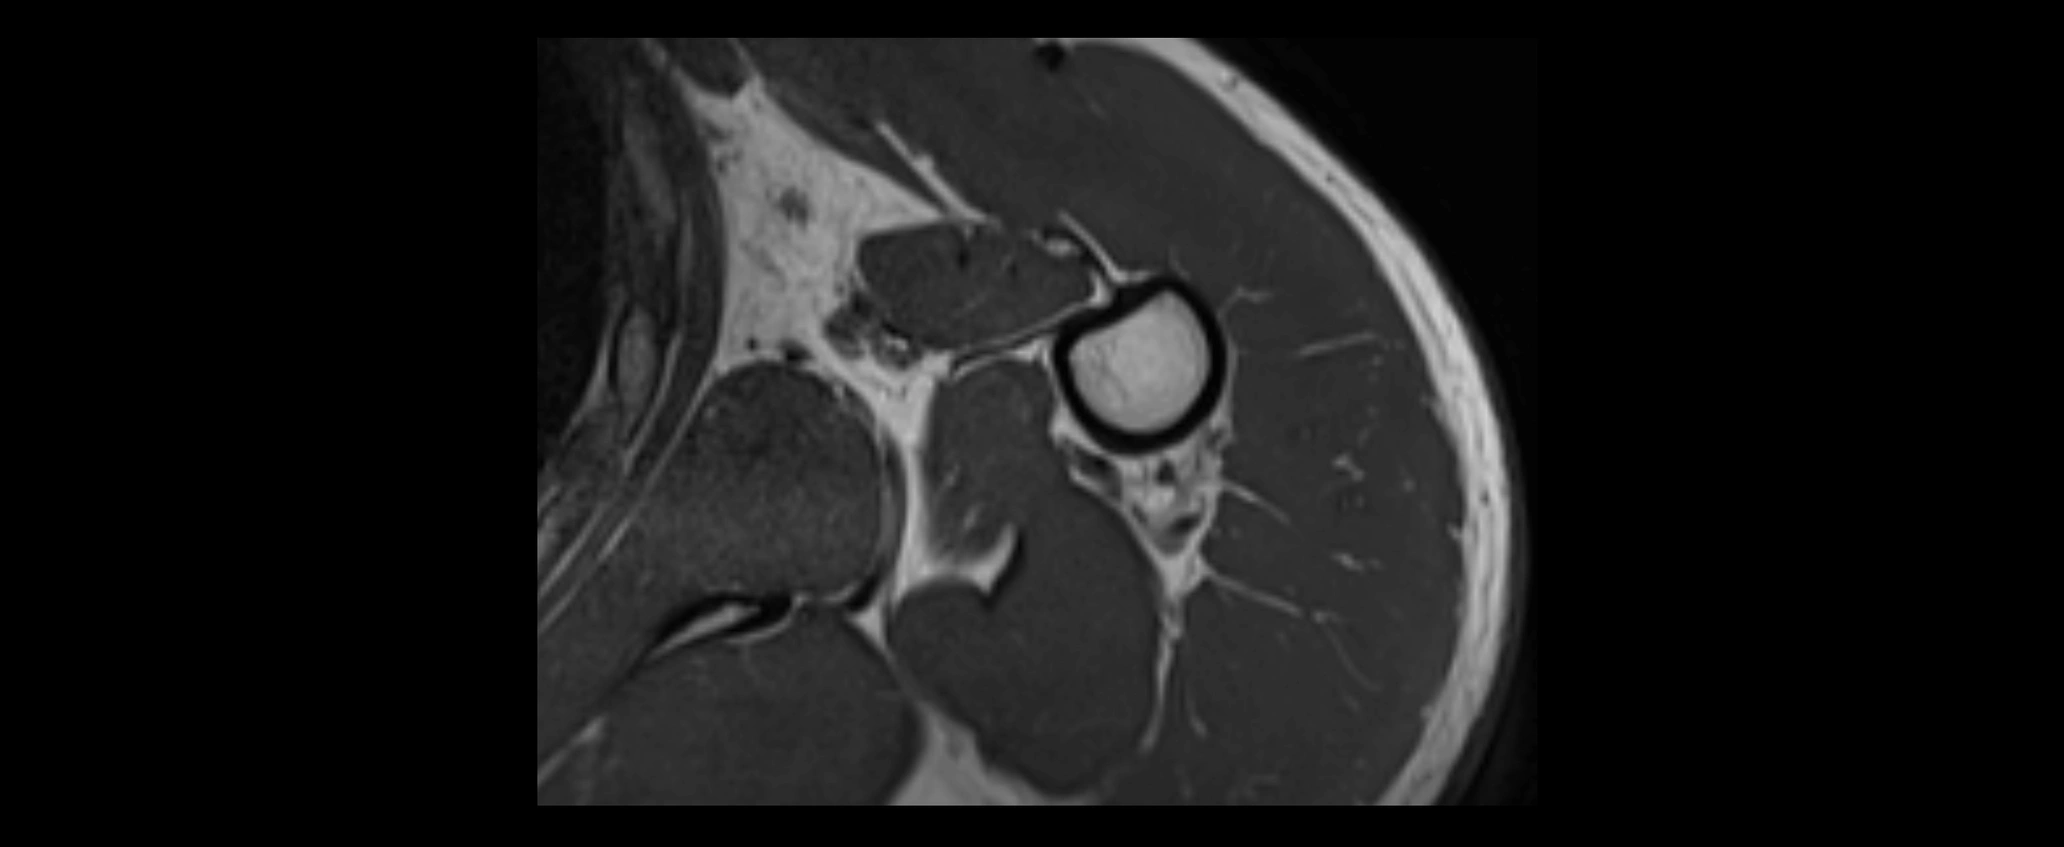

MRI images

image

CT Appearance

Non-Contrast CT:

• Ligament: Not directly visualized due to small size and low density.

• Bony landmarks: Lateral clavicle and acromion clearly seen; cortical margins well defined.

• Pathology: Detects fractures, joint subluxation, osteophytes, and degenerative changes.

• Alignment assessment: Evaluates AC joint spacing and clavicular displacement.